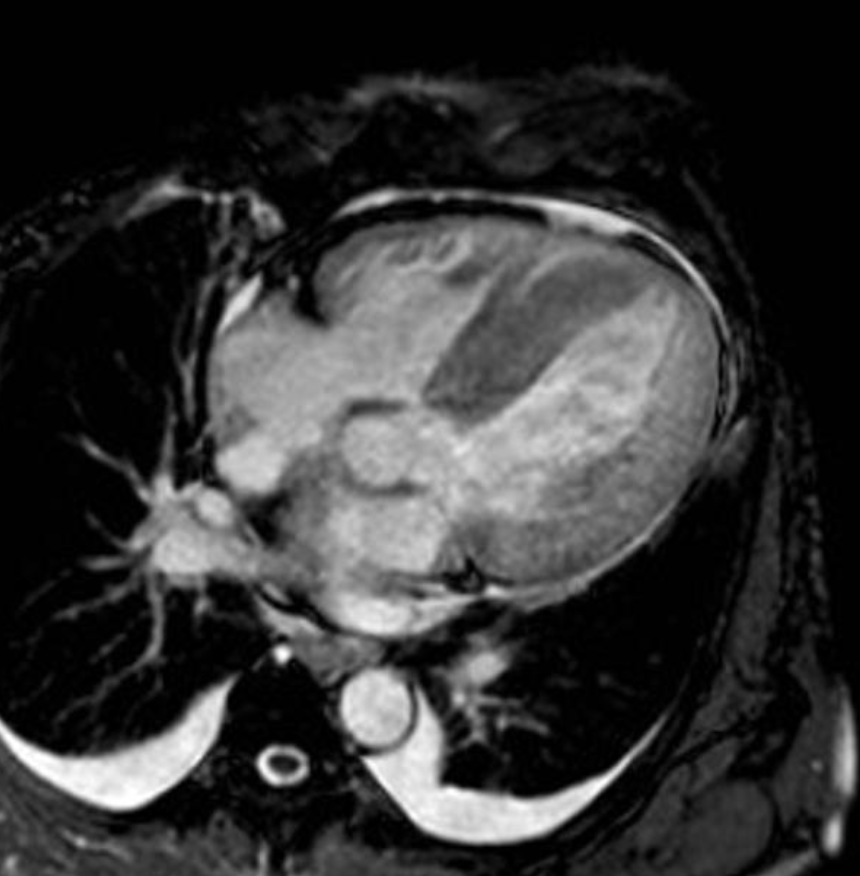

6) 심장 자기공명영상

- 심장자기공명영상 : 민감도가 높은 검사법